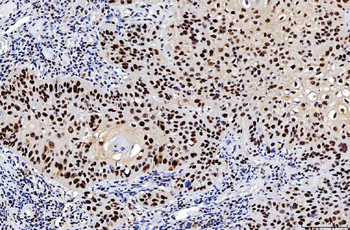

![Anti-FEN1 [SAIC-21C-4]](/images//pub/media/catalog/product/NewWebsite/35/orb1089994_1.png)

![Anti-FEN1 [SAIC-21C-4]](/images/pub/media/catalog/product/NewWebsite/35/orb1089994_2.png)

![Anti-FEN1 [SAIC-21C-4]](/images/pub/media/catalog/product/NewWebsite/35/orb1089994_3.png)